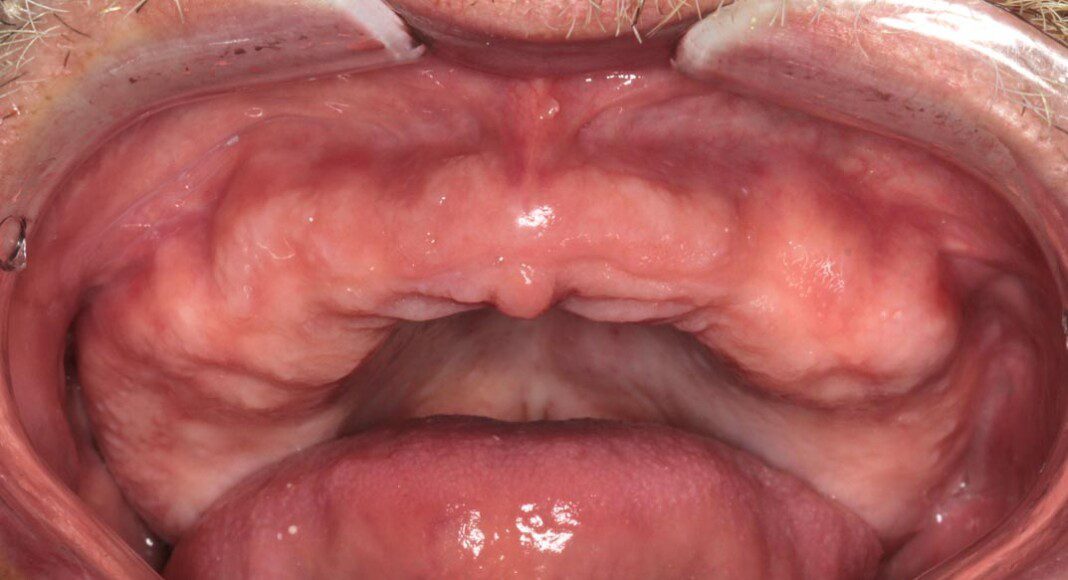

Three months post, first surgery the patient returns for implant uncovering and these are the impression copings preparing for the fixed temporary bridge.